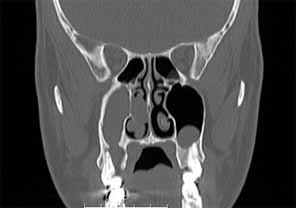

- 歯根尖/歯周領域における放射線透過性を示すCTスキャン(画像3c)

慢性副鼻腔炎の治療には、歯の感染の除去が含まれます。これには、歯内療法、歯周治療、または外科的な処置による抜歯が必要になる場合があります。感染の予防が困難な場合は、抜歯が必要になる場合があります。その後、副鼻腔の交通を特定するために、Vamevalテストを実施する必要があります。患者との良好なコミュニケーションが極めて重要であり、治癒を確実にするためには、より根本的な治療が必要になる場合が多いです。急性副鼻腔炎の場合は治療が必要です。PC予防と、ネザリルなどの充血除去薬を組み合わせた、1回限りの手術が行われる。より大きな交通や瘻孔が慢性化している場合は、鼻の矯正手術(画像4a~4e)が必要となります。場合によっては、耳鼻咽喉科医によるFESS手術と同時に行うこともできます。FESS手術では、鼻の側壁にある開口部を外科的に広げて換気を確保し、閉塞を防止します。